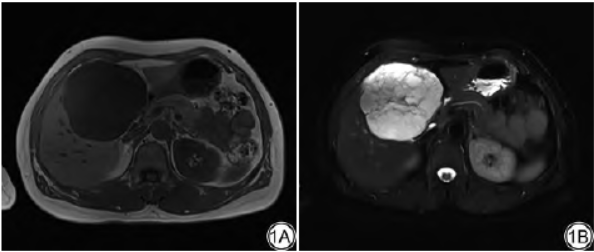

既往史:10年前因“畸胎瘤”行腹腔镜下卵巢切除术。上腹部MRI检查示:肝内见巨大类圆形混杂信号影,病灶大小约:8.7cm×7.7cm×11.1cm,T1呈低信号,T2压脂呈高信号,内见类圆形更高信号及分隔样低信号,增强扫描动脉期可见斑片样、结节样强化,门脉期、延迟期强化范围逐渐增大,强化信号不均匀(图1A~1E)。影像诊断:考虑血管源性肿瘤可能性大。

图1女,50岁,肝脏硬化性脂肪肉瘤。1A:T1WI病灶呈低信号;1B:T2WI压脂病灶呈高信号,内见分隔样低信号;1C:增强扫描动脉期可见斑片样、结节样强化;1D:门脉期强化范围增大;E:延迟期强化范围进一步增大,强化信号不均匀。1F:病理图,可见致密的胶原纤维化区域,梭形细胞有一定的异形性,核深染,不规则(HE×100)。